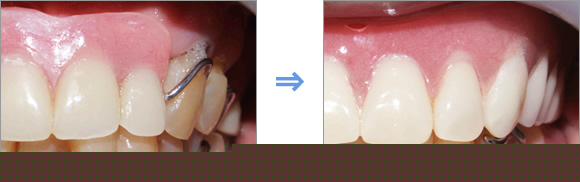

Before:歯と歯ぐきの境目に歯垢や歯石が付着し、歯ぐきが赤く腫れています。

Brushing:ブラッシング指導を行い、歯ぐきの腫れを改善します。

Treatment:歯石を取り除くことで、歯ぐきの慢性炎症を消炎します。

After:赤くなっていた歯ぐきは健康なピンク色に改善されています